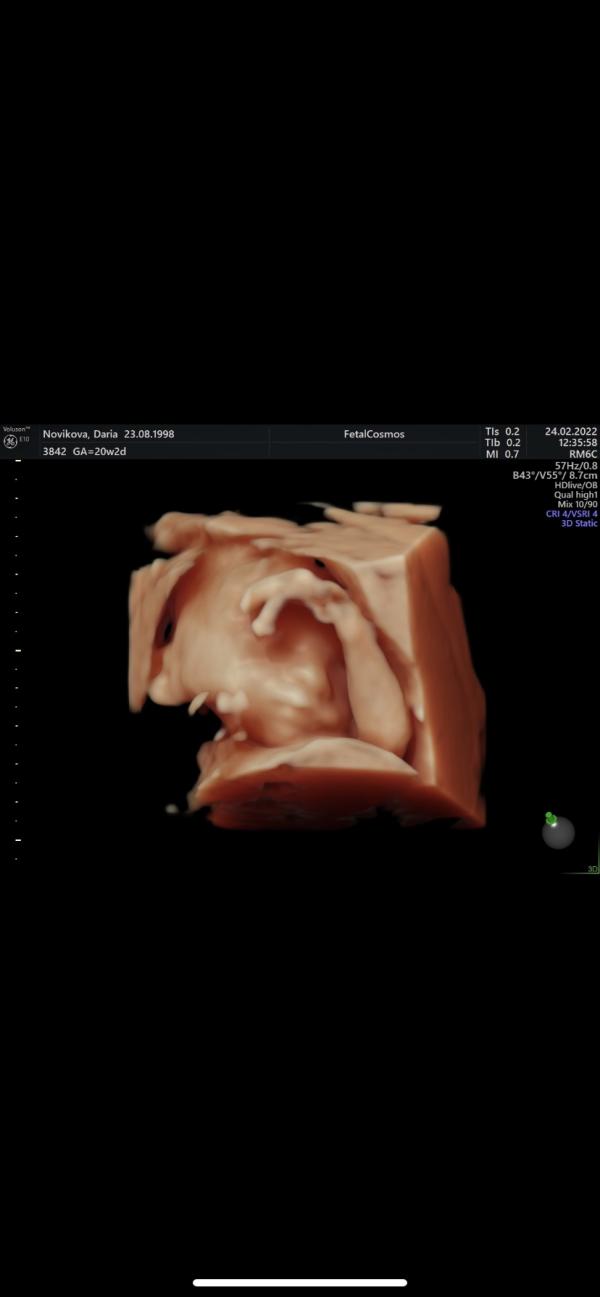

Был сегодня второй скрининг. Малыш постоянно позировал для фото, но нужными частями не поворачивался. 😁 по этому пробыли в кабинете около часа. Все же лучше, чем в прошлый раз (скрининг длился 2,45ч, малыш не хотел поворачиваться так, как нужно)